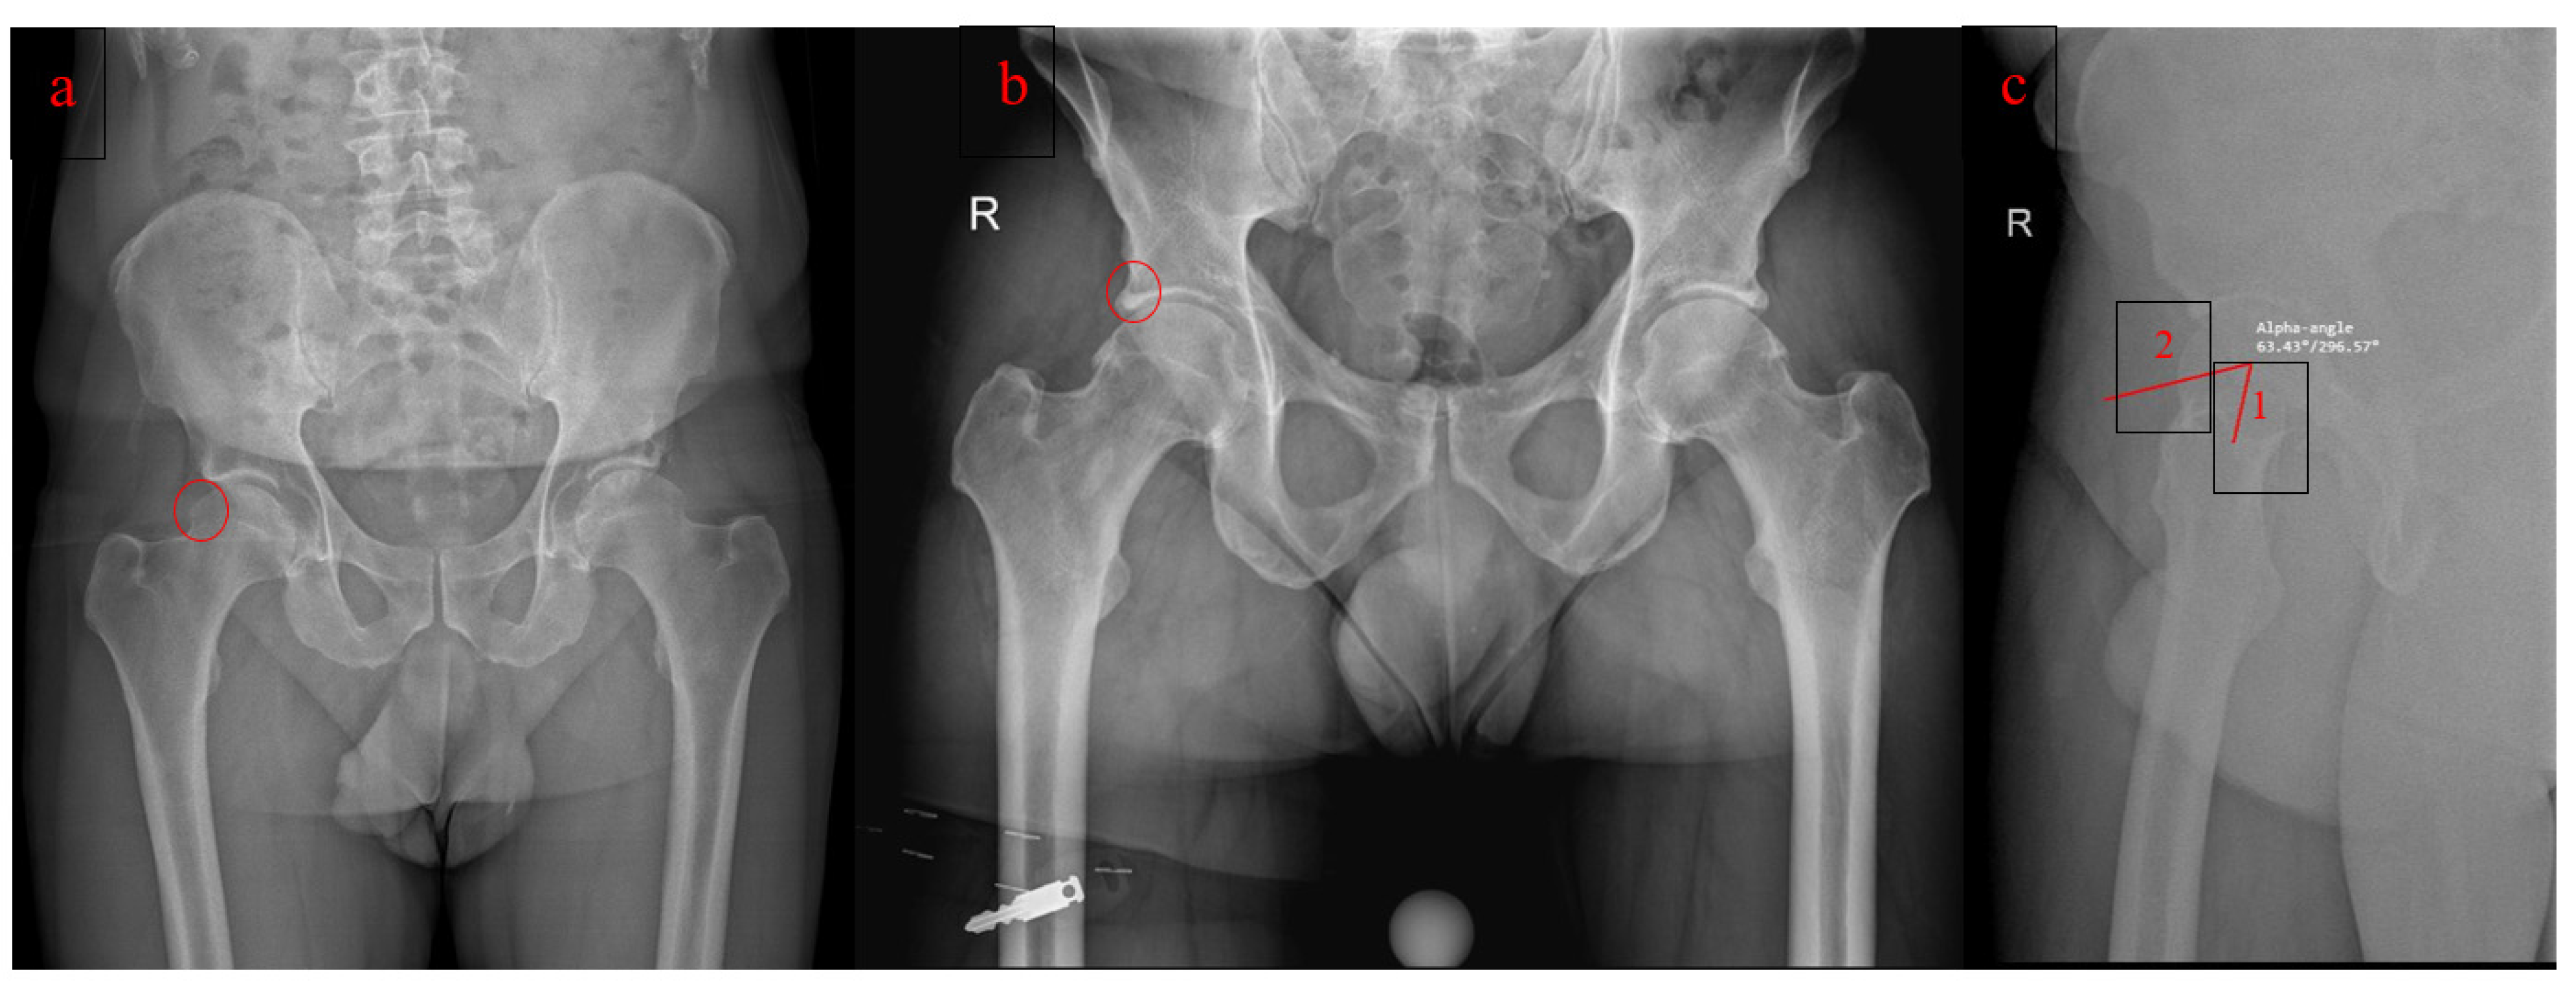

- Laborie, L.B.; Lehmann, T.G.; Engesæter, I.Ø.; Sera, F.; Engesæter, L.B.; Rosendahl, K. The alpha angle in cam-type femoroacetabular impingement: New reference intervals based on 2038 healthy young adults. Bone Joint J. 2014, 96, 449–454. [Google Scholar] [CrossRef]

- Fioruzzi, A.; Acerbi, A.; Jannelli, E.; Ivone, A.; Fontana, A. Interobserver and intraobserver reliability of a new radiological classification for femoroacetabular impingement syndrome. Musculoskelet Surg. 2020, 104, 279–284. [Google Scholar] [CrossRef]